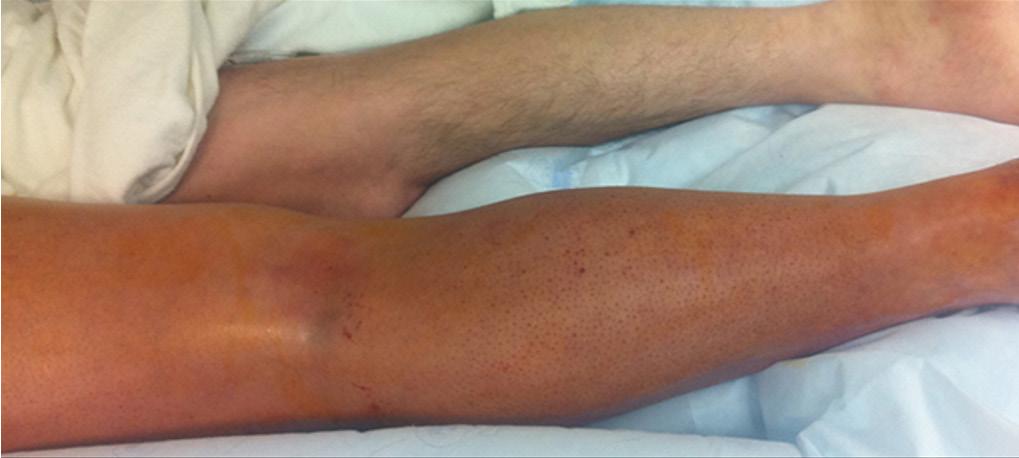

Hay edema y eritema difusos en el miembro inferior izquierdo. El diámetro de la pantorrilla izquierda es visiblemente mayor que el de la derecha

Figura 50. Trombosis venosa profunda (TVP)